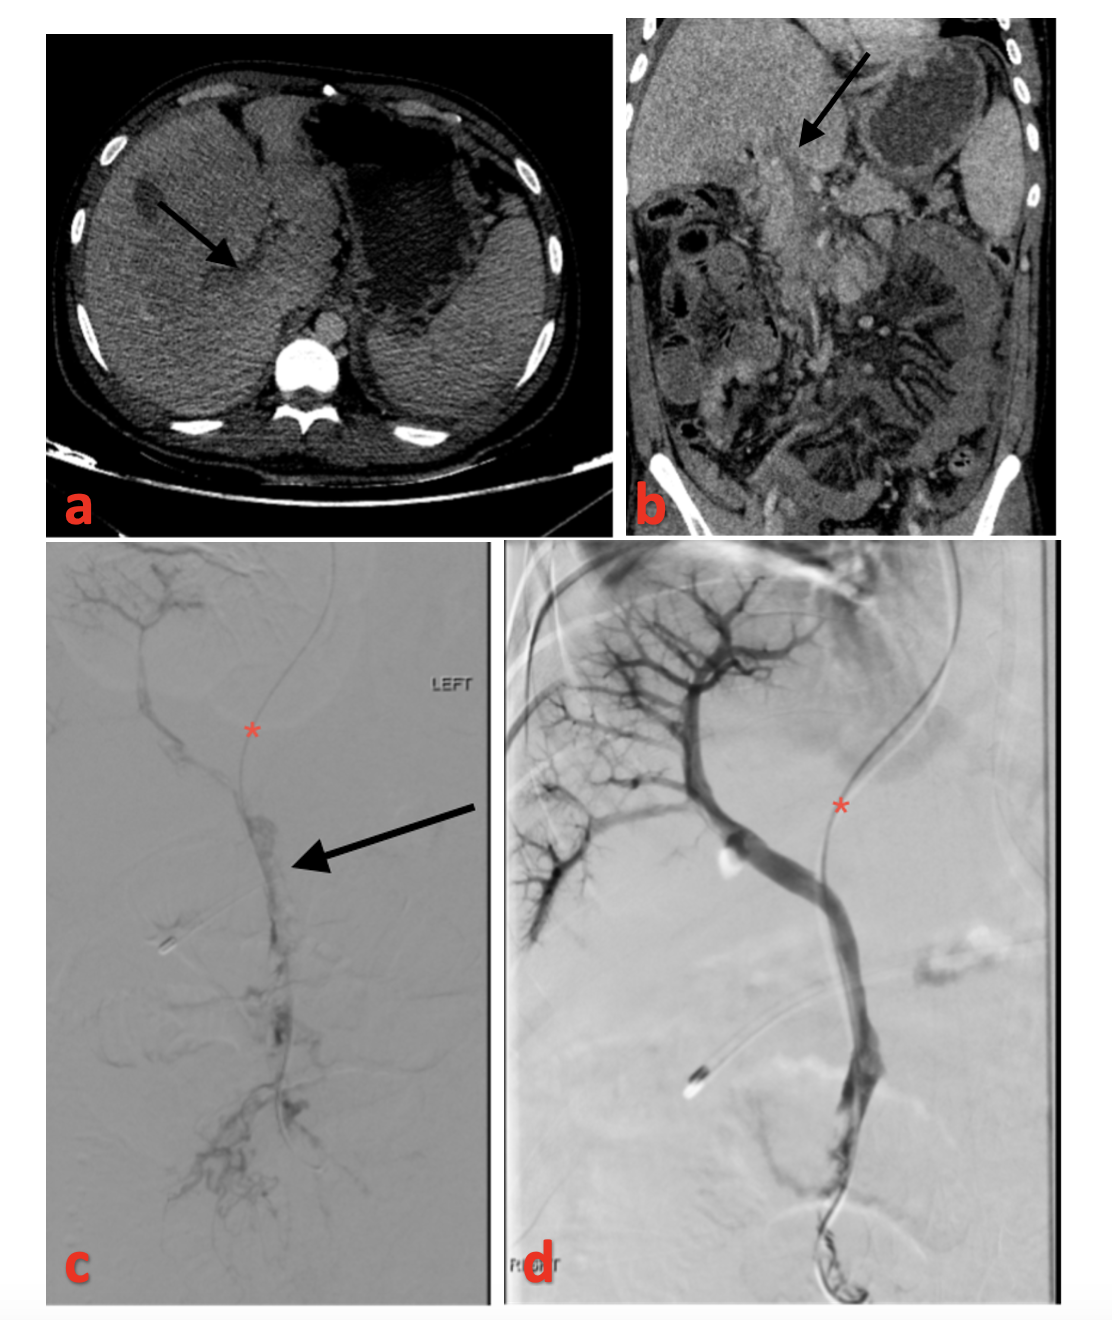

Technical success was achieved in 4 patients; however, out of the 4 patients, 2 (patients 5 and 6) worsened clinically and progressed to bowel gangrene. Klinger et al had a similar result in 2 out of 17 patients.33 The 2 patients (patients 2 and 4) in whom recanalization was achieved and improved clinically were diagnosed promptly, and intervention was done early (within 2 days of symptom onset) (Figure 2). The 2 patients who had clinical worsening had bowel wall thickening on preprocedural CT, although there was mucosal enhancement and no clinical signs of peritonitis. Surgery consultation was sought, and they were inclined toward nonoperative management as there were no obvious clinical signs of gangrene. A combined surgical approach and local thrombolysis were described in a small case series by Loss M et al.34 The combined approach may benefit patients who already have impending signs of bowel ischemia.

Overall clinical improvement was seen in 4 patients (66.6%), although 1 patient underwent bowel resection (Patient 5, Figure 3), and in 1 patient the PV was not recanalized (Patient 3) and had cavernoma formation on follow-up.